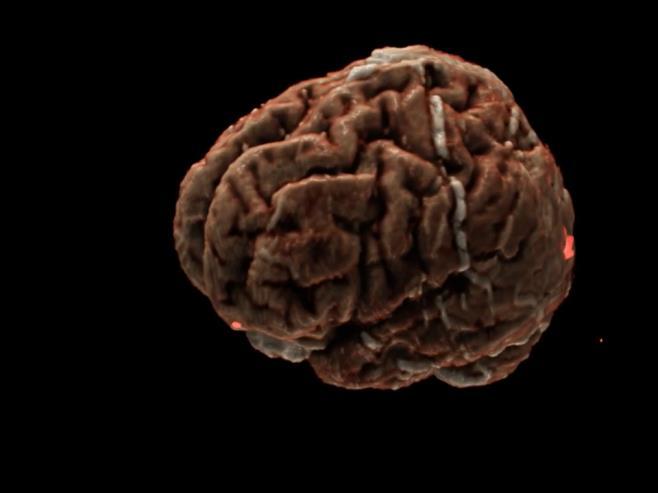

- Abnormality detection, acute infarction, acute hemorrhage, mass effect

Sagittal T1W, FLAIR, TraceW, & ADC

Processing mpMRI data after repositioning via landmarks & skull stripping

AI system

Trained on 25,000 MRI studies

Oncology risk prediction Brain tumor and mets